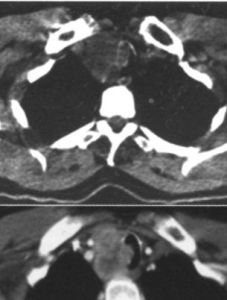

影像學檢查是定位診斷的主要方法,還可同時監測對治療的反應。目前,CT、磁共振成像(MRI)、超聲檢查(US)、內鏡超聲(EUS)等檢查尚未被進一步評價。生長抑素受體顯像的敏感性可根據腫瘤的類型而有所不同,其對於垂體瘤、胃腸胰腺神經性內分泌腫瘤,敏感性超過75%,但對胰島素瘤僅為中度敏感(40%~75%)。